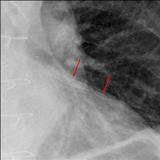

Calc Ao valve & LtA

Date: 01/26/2009

Views: 3000